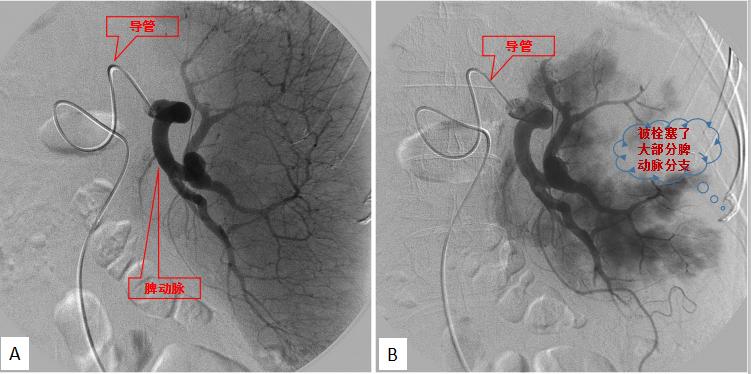

部分性脾栓塞术,A栓塞前造影,B栓塞后造影

PSE只需要局部麻醉皮肤,用不到2毫米的针穿刺股动脉,将导管在电视透视的监视下选择性插入脾动脉,造影确定情况后,选用合适的栓塞剂经导管注入脾脏下极及外周的脾动脉分支内,将其栓塞就算完成了。被栓塞的那部分脾组织,将会因缺血而发生梗死,最后可被吸收消失,它那强烈的吞噬血细胞的功能也就随之而灭失,治疗作用也就实现了。